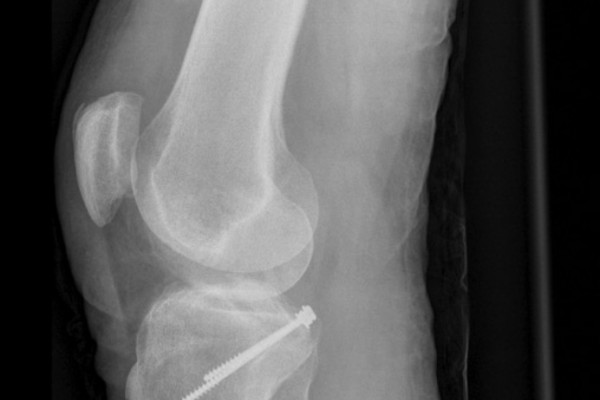

Versorgung knöcherner Ausrisse des vorderen und hinteren Kreuzbandes

In seltenen Fällen kommt es zu knöchernen Ausrissen des vorderen Kreuzbandes. Diese Form der Verletzung ist bei Kindern häufiger als bei Erwachsenen. Hierbei bleibt das Kreuzband intakt während es mit einem knöchernen Bruchstück aus dem Schienbeinkopf ausreißt. In diesen Fällen kann das ausgerissene Knochenstück und somit auch das Kreuzband mittels einer Schraube oder durch stabile Nähte die durch Bohrkanäle ausgeleitet werden refixiert werden. Somit ist eine vollständige Ausheilung dieser schweren Verletzung möglich.